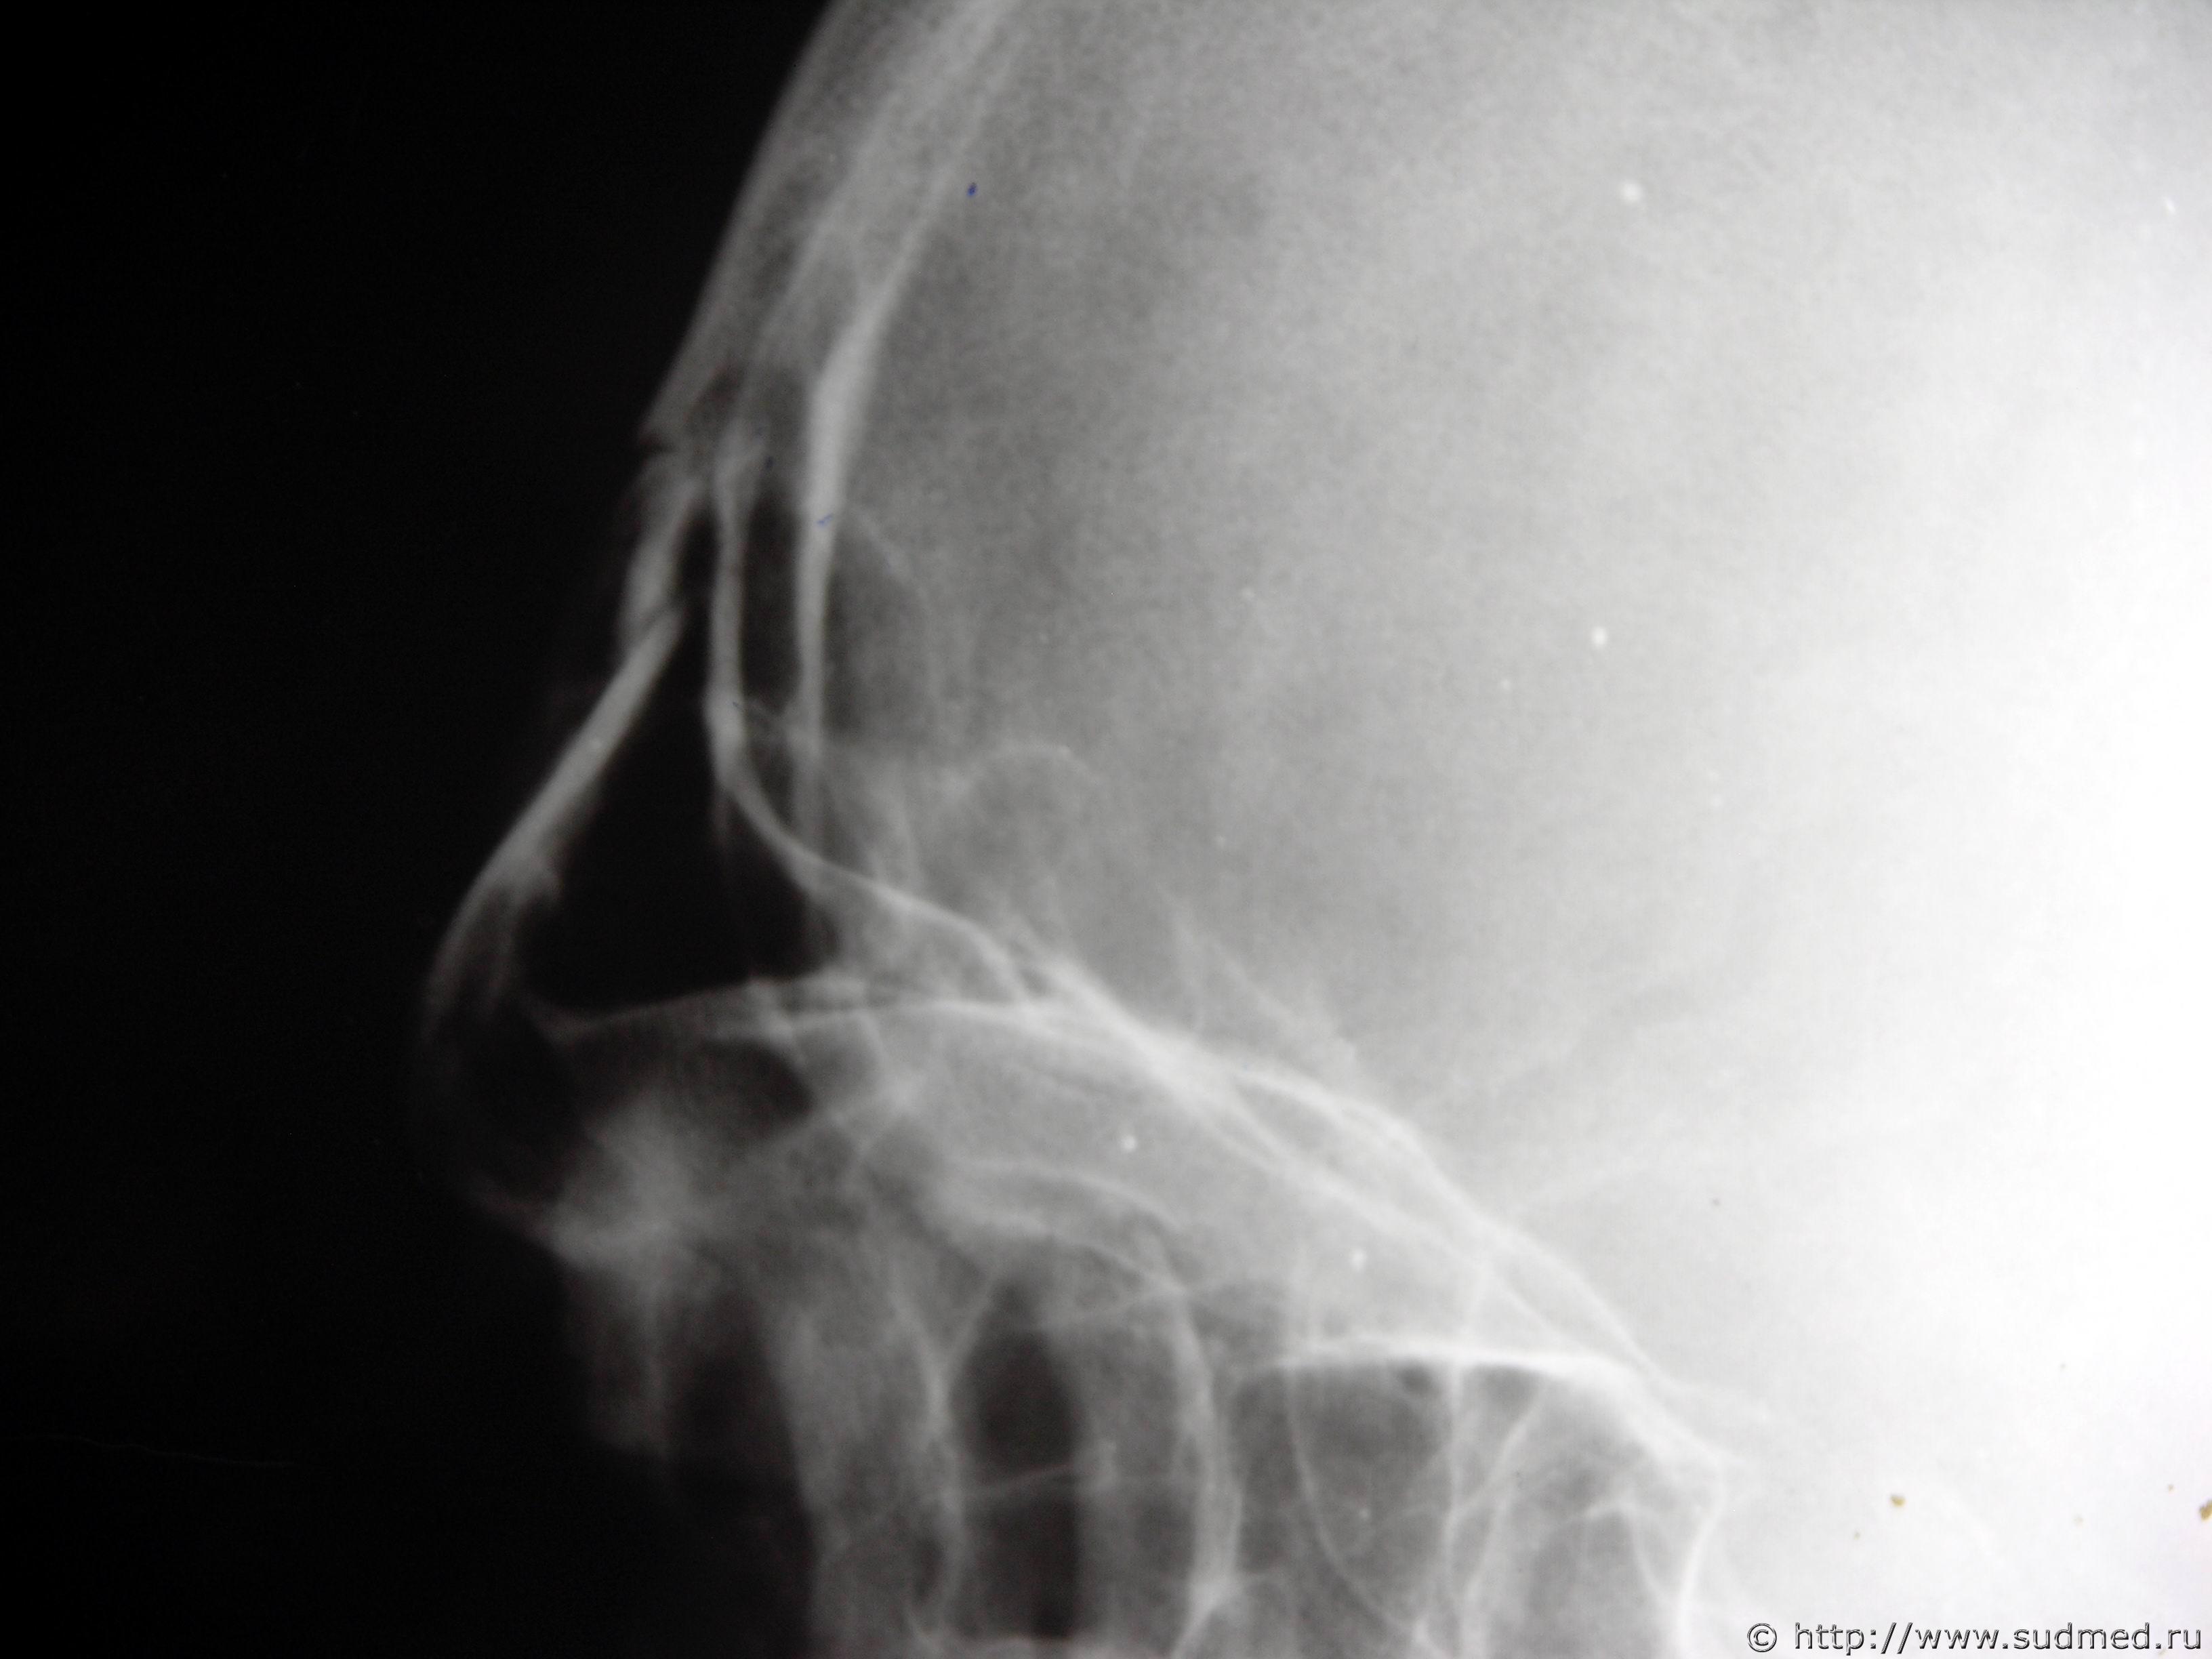

У мужчины 55 лет были обнаружены телесные повреждения: "...В лобной области определяется ушибленная рана с неровными краями, ослизнена..." На На рентгенограммах черепа в 2-х проекциях от 09.02.2016г. №... определяется перелом лобной кости в боковой проекции.

Согласно п. 6.1.2 ... перелом лобной кости квалифицируется как тяжкий вред. Исключения составляют переломы лицевых косте и изолированные переломы наружной костной пластинки... В комментариях указывается, что в эту группу включаются все переломы внутренней костной пластинки. Как видно на рентгенограммах в данном случае внутренняя костная пластинка не повреждена. Но ни в критериях, ни в комментариях про переломы лобной пазухи ни чего не сказано.

ВОПРОС: Как по Вашему мнению подойти к квалификации степени тяжести вреда здоровью в данном случае - как к перелому лобной кости и, соответственно, тогда тяжкий вред или при не поврежденной внутренней костной пластинке свода черепа по длительности расстройства здоровья и тогда средний?